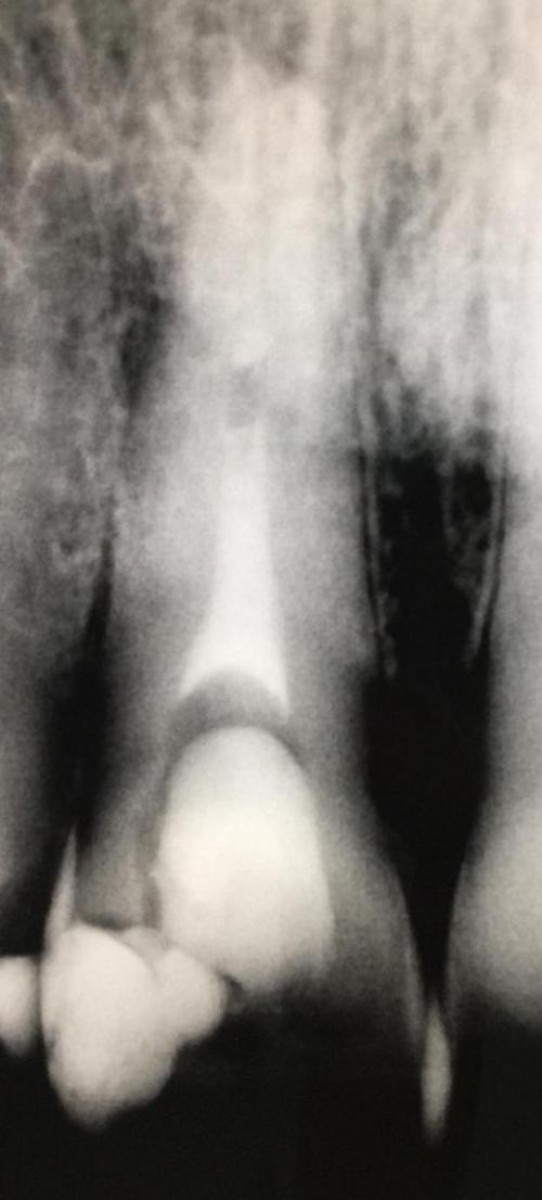

Restoration of endodontically treated maxillary central incisors with class III defects is a challenging procedures because the choice of which rehabilitation to choose depends on the amount of structure remaining. The aim is to give new functionality to the element but also to obtain a good aesthetic result, since we have to deal with an element of the frontal sector. Moreover, endodontically treated anterior teeth were found to have an high risk of biomechanical failure due to shear forces.

Seventy-two extracted human maxillary central incisors were endodontically treated and bi-proximal Class III cavities were prepared. They were randomly allocated to six groups (n = 12): direct restoration with composite (group C); direct restoration with composite and additional glass-fiber post (group CP); ceramic veneer restoration (group V); ceramic veneer restoration with endodontic glass-fiber post (group VP); ceramic crown restoration (group Cr); ceramic crown restoration and additional glass-fiber post (group CrP). They were exposed to thermomechanical loading (TML: 1.2 million cycles, 1 to 50 N; 6000 thermal cycles between 5°C and 55°C for 1 min each), and subsequently linearly loaded until failure (Fmax [N]) at an angle of 135° and 3 mm below the incisal edge on the palatal side. Statistical tests were performed using the Kruskall-Wallis and Mann-Whitney U-Test.